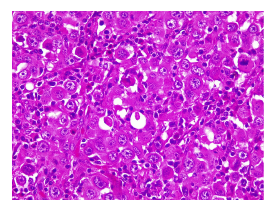

Histológicamente puede tener varios patrones, desde nódulos expansivos, quistes y papilas, hasta áreas sólidas y cribiformes. Las células son redondas a poligonales, tienen un tamaño intermedio y presentan una escasa tasa de mitosis. Usualmente no se observa necrosis. La cantidad de mucina intracelular o extracelular varía según el tumor y tiende a ser muy poco notoria en las fases iniciales o en las zonas sólidas.

El diagnóstico ha evolucionado con el tiempo y el uso de las técnicas de inmunohistoquímica ha significado una mayor claridad, utilizando un panel amplio para lograr identificar su histogénesis, ya que a veces es imposible diferenciarlo histológicamente de una metástasis de adenocarcinoma de mama. Los marcadores que suelen ser positivos (mas no específicos) son el CK7, CK8, CK18, AE1/AE3, CAM5.2, EMA, GCDFP-15, estrógenos y progesterona. Lo más característico es la expresión de marcadores neuroendocrinos como la sinaptofisina y la cromogranina 10.

El adenocarcinoma apocrino de glándula sudorípara es una inusual neoplasia cutánea de anexos, que se manifiesta histológicamente con signos inequívocos de secreción por decapitación o gránulos de cimógenos citoplasmáticos. Además, no debe detectarse a nivel microscópico ninguna otra lesión con diferenciación apocrina, como en el caso de siringocistadenocarcinoma papilífero, carcinoma mucinoso, carcinoma papilar digital o neoplasias benignas como cilindroma, espiradenoma y tumor mixto apocrino. Tampoco debe estar asociado u originado en una glándula especializada: las de Moll, las ceruminosas, las anogenitales y las de tipo mamario) 11.

Histológicamente, el tumor está conformado por células epiteliales con abundante citoplasma granular eosinófilo, parcialmente vacuolado. Puede tener diferenciación ductal y secreción por decapitación. El pleomorfismo y las figuras mitóticas son variables. El nucléolo tiende a ser conspicuo. En algunas ocasiones puede adoptar patrones morfológicos con células en anillo de sello o aspecto histiocitoide, similar al carcinoma de células en anillo de sello o histiocitoide periorbitario. En la inmunohistoquímica, las células tumorales son positivas para citoqueratina 7 y tienen expresión variable para CEA, S100, EMA, estrógenos y progesterona 12. Anticuerpos como el EKH5 y el EKH6 son específicos para los órganos con secreción ecrina y han demostrado ser útiles 5. Otros criterios para el diagnóstico histológico incluyen material positivo para PAS y resistente a la diastasa en células luminales, positividad inmunohistoquímica para GCDFP-15 6, así como expresión positiva para el receptor de andrógenos.